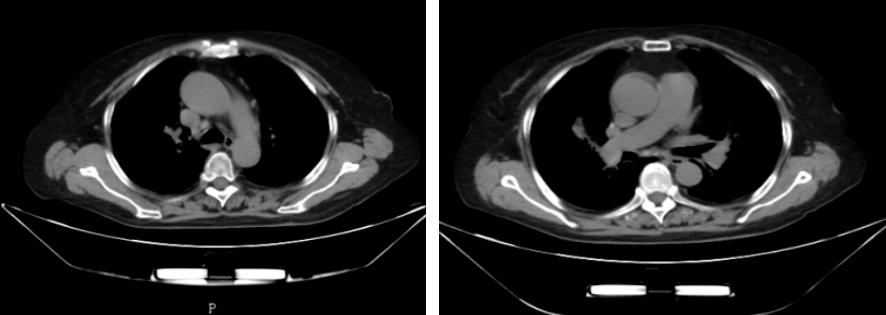

此次发病的半年前,患者也曾出现胸闷、喘息,活动后加重,但未治疗。这一次,我院门诊行胸部CT检查提示为:1.双肺炎症,2.心影增大 3.纵膈内稍大淋巴结 4.两侧胸膜局部增厚 5.脂肪肝,肝右叶钙化灶,建议再次住院治疗,门诊以「气管支气管狭窄并右肺中叶不张原因待查:结核?结节病?」为诊断收入我科。辅助检查情况为:胸部CT(图4)提示:双肺炎症 2.心影增大 3.纵膈内增大淋巴结,部分钙化 4.两侧胸膜局部增厚 5.脂肪肝,肝右叶钙化灶

图4:第二次住院胸部CT